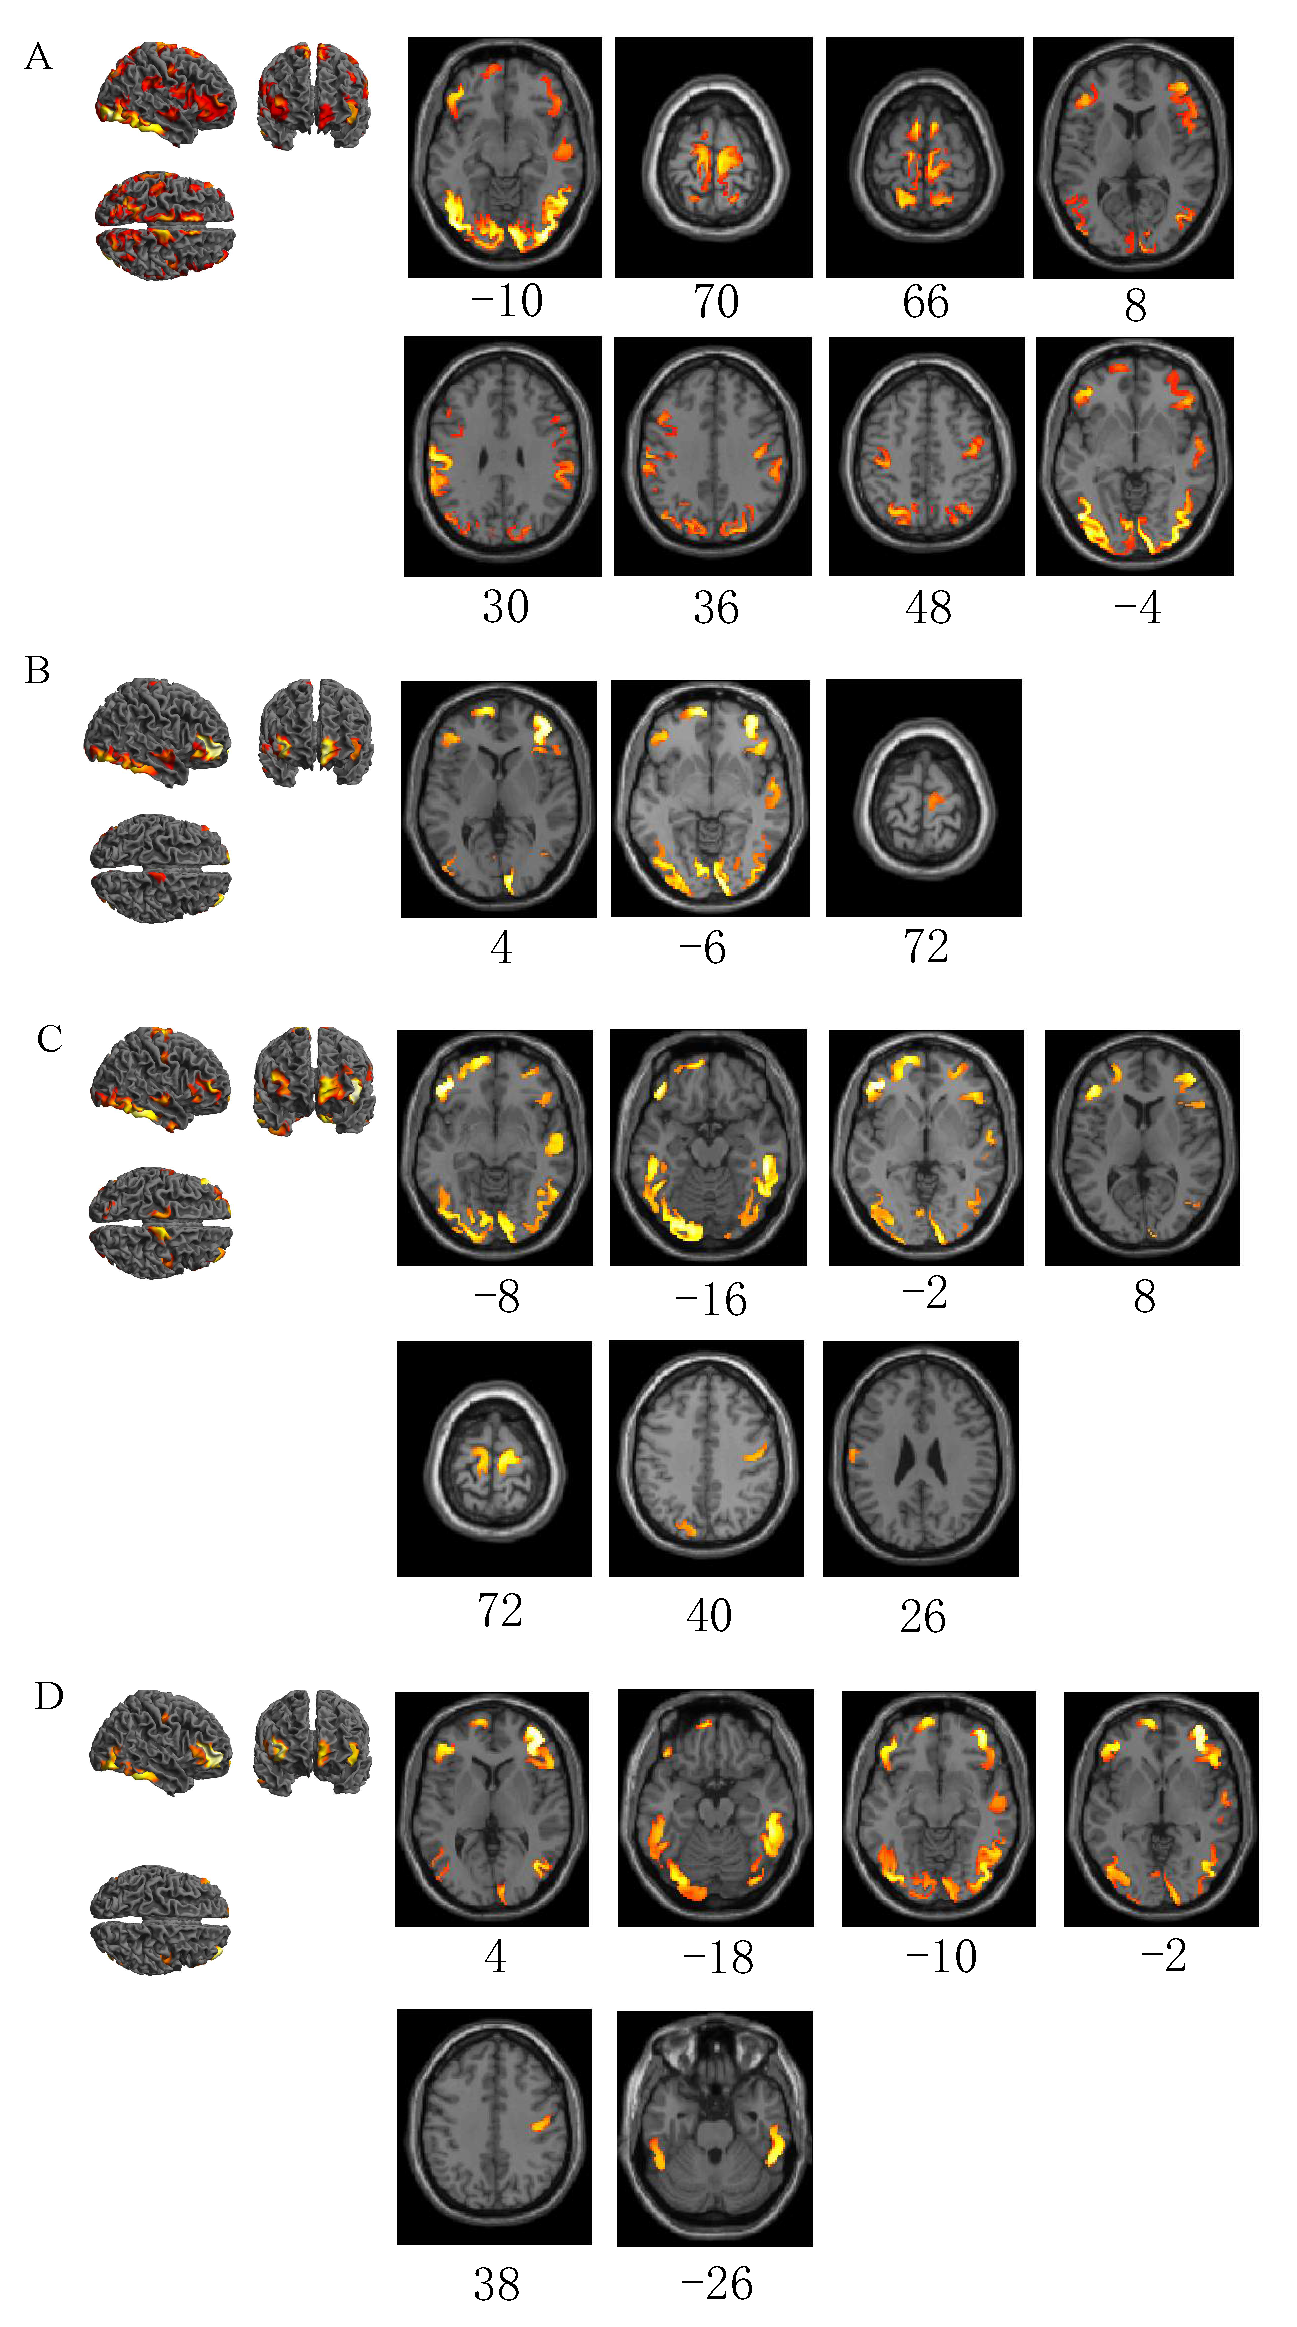

3.1. Emergency Braking Activates Brain Areas in Four Driving Conditions

| Emergency braking in normal driving | 46 | −4 | −34 | 39,965 | 24.71 | R | Inferior temporal gyrus |

| −48 | −70 | 32 | 232 | 8.25 | L | Angular gyrus | |

| 0 | −32 | 24 | 150 | 5.89 | L | Posterior cingulate gyrus | |

| −30 | 6 | −16 | 83 | 4.79 | L | Superior temporal gyrus | |

| Emergency braking in visual distraction driving | 44 | 50 | 4 | 5360 | 20.97 | R | Middle frontal gyrus |

| −44 | 0 | −34 | 6255 | 20.74 | L | Inferior temporal gyrus | |

| −16 | 62 | 6 | 4188 | 19.21 | L | Superior frontal gyrus, dorsolateral | |

| 44 | −4 | −32 | 5567 | 17.97 | R | Inferior temporal gyrus | |

| 64 | −10 | 20 | 750 | 8.66 | R | Postcentral gyrus | |

| −12 | 2 | 66 | 283 | 7.99 | L | Supplementary motor area | |

| −60 | −18 | 24 | 543 | 7.73 | L | Postcentral gyrus | |

| −12 | −24 | 74 | 206 | 7.57 | L | Paracentral lobule | |

| 8 | −22 | 72 | 516 | 7.55 | R | Paracentral lobule | |

| −52 | −42 | 26 | 164 | 5.61 | L | Supramarginal gyrus | |

| −22 | 22 | −20 | 186 | 5.29 | L | Inferior frontal gyrus, orbital part | |

| Emergency braking in auditory distraction driving | 46 | −4 | −34 | 5446 | 20.72 | R | Inferior temporal gyrus |

| −20 | 62 | 6 | 4540 | 19.01 | L | Superior frontal gyrus, dorsolateral | |

| 14 | 62 | 6 | 5376 | 18.56 | R | Superior frontal gyrus, medial | |

| −44 | −2 | −34 | 6045 | 18.23 | L | Inferior temporal gyrus | |

| −62 | −10 | 24 | 976 | 10.17 | L | Postcentral gyrus | |

| 64 | −8 | 18 | 929 | 10.10 | R | Postcentral gyrus | |

| 10 | −18 | 72 | 621 | 9.85 | R | Supplementary motor area | |

| −12 | −24 | 74 | 640 | 9.14 | L | Paracentral lobule | |

| 40 | −68 | 46 | 245 | 7.46 | R | Angular gyrus | |

| −28 | −68 | 52 | 197 | 6.86 | L | Superior parietal gyrus | |

| 62 | −40 | 22 | 132 | 5.82 | R | Superior temporal gyrus | |

| Emergency braking in cognitive distraction driving | 44 | 50 | 4 | 6376 | 26.65 | R | Middle frontal gyrus |

| −42 | 0 | −34 | 6369 | 23.47 | L | Inferior temporal gyrus | |

| 46 | −4 | −36 | 6456 | 22.53 | R | Inferior temporal gyrus | |

| −16 | 62 | 4 | 5164 | 21.11 | L | Superior frontal gyrus, dorsolateral | |

| −62 | −12 | 24 | 1002 | 10.69 | L | Postcentral gyrus | |

| 56 | −20 | 26 | 1219 | 10.35 | R | Supramarginal gyrus | |

| 40 | −16 | 38 | 403 | 8.76 | R | Postcentral gyrus | |

| 12 | −26 | 68 | 359 | 8.13 | R | Paracentral lobule | |

| −12 | −26 | 74 | 527 | 7.41 | L | Paracentral lobule | |

| −54 | −62 | 8 | 201 | 7.03 | L | Middle temporal gyrus | |

| −30 | −68 | 50 | 138 | 6.05 | L | Superior parietal gyrus | |

| 40 | −68 | 46 | 140 | 5.94 | R | Angular gyrus | |

| 10 | 4 | 68 | 107 | 5.08 | R | Supplementary motor area | |